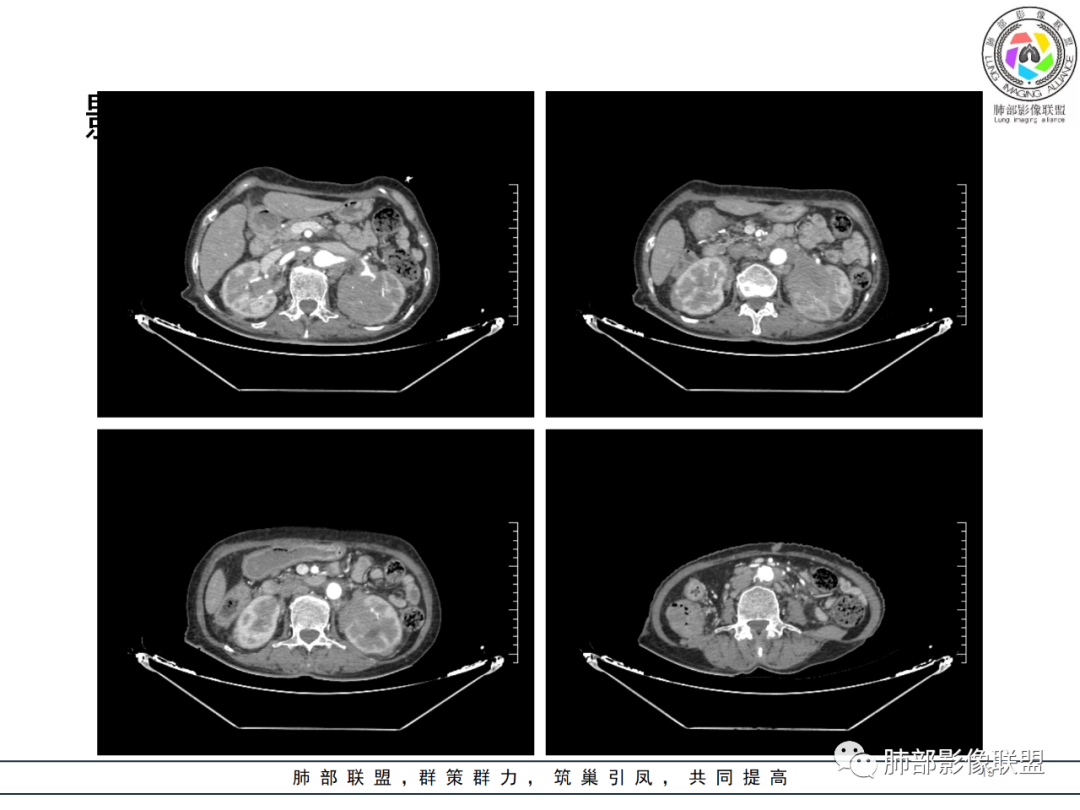

影像资料

老年女性,发热起病,两肺散在斑片状影,三个月后两肺病灶进展,支气管血管束增厚,结合发热病史、实验室检查LCH增高,肾脏及腹膜后淋巴结肿大,结合以上综合考虑符合淋巴瘤表现。

老年女性,发热,白细胞不高,CRP增高,LDH增高,糖尿病。两肺支气管血管束周围实变、GGO,支气管相对通畅,提示淋巴间质或血管来源。三个月明显进展伴双肾浸润性病变、腹膜后淋巴结肿大,轻-中等程度强化。考虑淋巴瘤,鉴别系统性疾病(IgD4、血管炎)。

老年女性,近期反复的发热,胸部CT基础尚可,心影增大,双肺下叶血管束增粗,3个月后复查 提示双肺多发磨玻璃密度影,并有磨玻璃影内部血管的穿行,双肺下叶血管束的增粗,纵隔窗下未见纵隔肿大的淋巴结,血管通畅,未见血管壁的增厚,左肾肿瘤?肺内病变不符合支气管束分布,暂不考虑吸入性,考虑淋巴管或血管源性病变。总体考虑非感染性病变可能性大,血管炎?淋巴瘤?

老年女性患者,发热就医,两肺片状影,沿支气管血管束分布,炎性指标升高,糖尿病基础,首诊考虑肺部感染合乎情理,这也是常见病!事实上,患者抗感染治疗好转出院。

三月后患者再次因发热就医,病灶在“原址”基础之上范围扩大,病灶增多(而非此起彼伏),就有些不同寻常,仅如此高龄,如此大范围感染,持续三月之久?太难以想象。